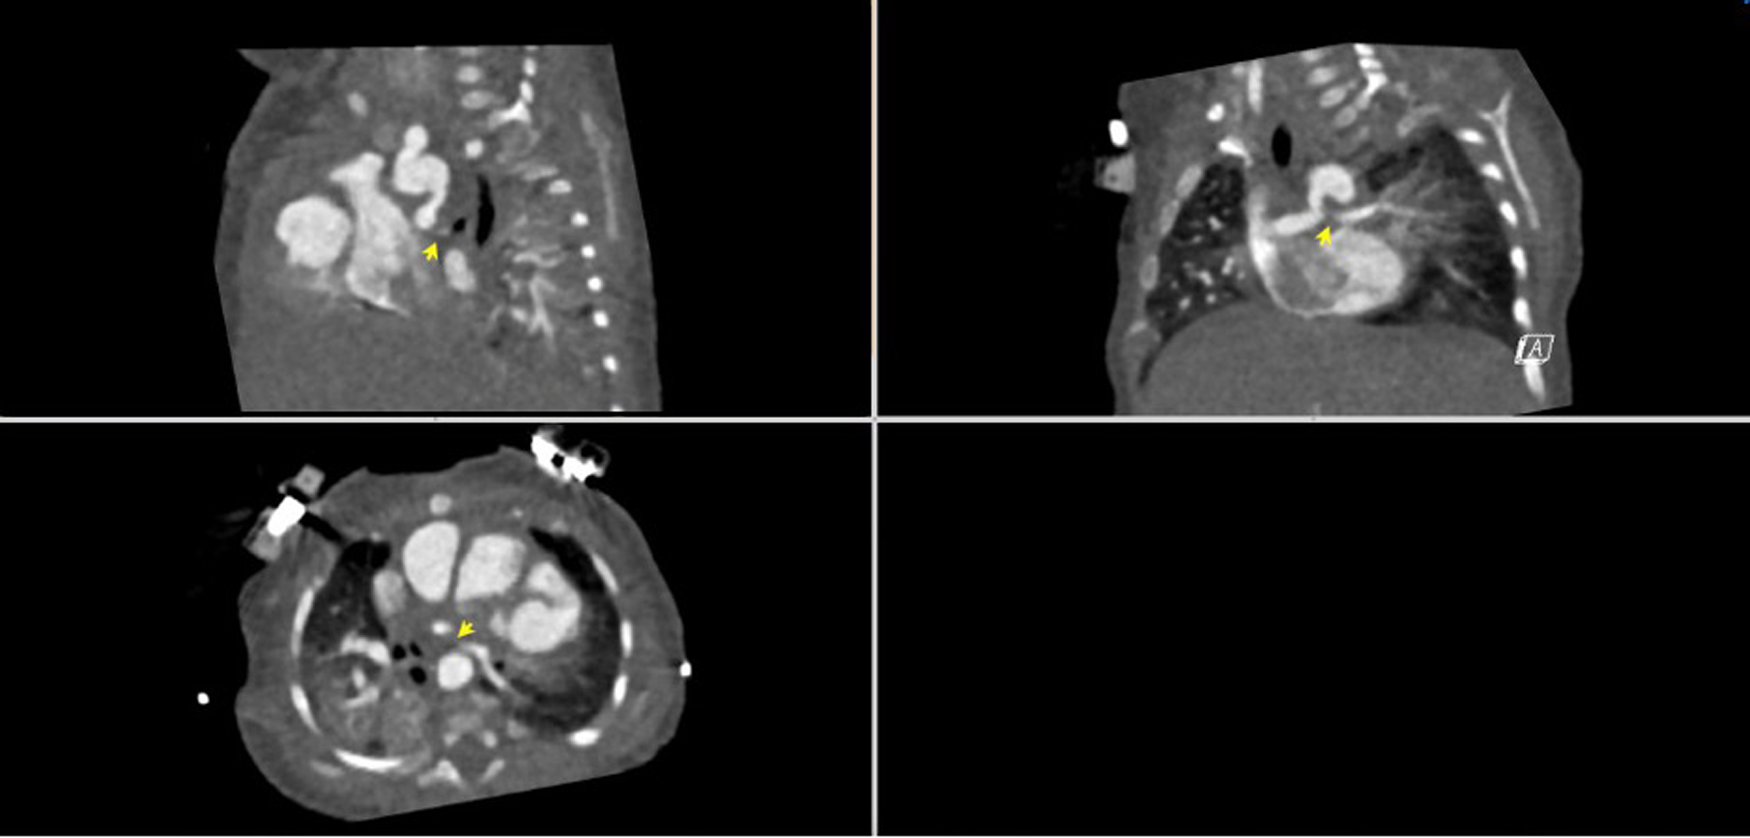

A 53-day-old, term 3-kg girl with a history of absent right AV connection, malposed great vessels, and pulmonary atresia underwent stage I palliation with a 3.5-mm aortopulmonary polytetrafluoroethylene (PTFE) graft shunt from the proximal aortic arch to the main pulmonary artery, atrial septectomy, and bilateral branch pulmonary artery patch augmentation on the sixth day of her life. Her postoperative course was complicated by ectopic atrial tachycardia, for which she was commenced on digoxin, and desaturation secondary to multilevel airway obstruction with mild supraglottic edema, laryngomalacia, and left vocal cord paralysis. As part of her assessment for low oxygen saturation, a CT scan was performed and demonstrated near-complete occlusion of her LPA and narrowing of her left main stem bronchus (Figure 1). Following multidisciplinary discussion with cardiovascular surgeons, the decision was made for the patient to undergo cardiac catheterization to recanalize the shunt and LPA and place a stent in the narrowed LPA.

Figure 1

CT angiogram demonstrating the aorta-to-pulmonary central shunt that originates from the under-side of the distal transverse artic arch immediately underneath the origin of the left subclavian artery. The proximal LPA is not visualized. The LPA reconstitutes distally and is diffusely hypoplastic.